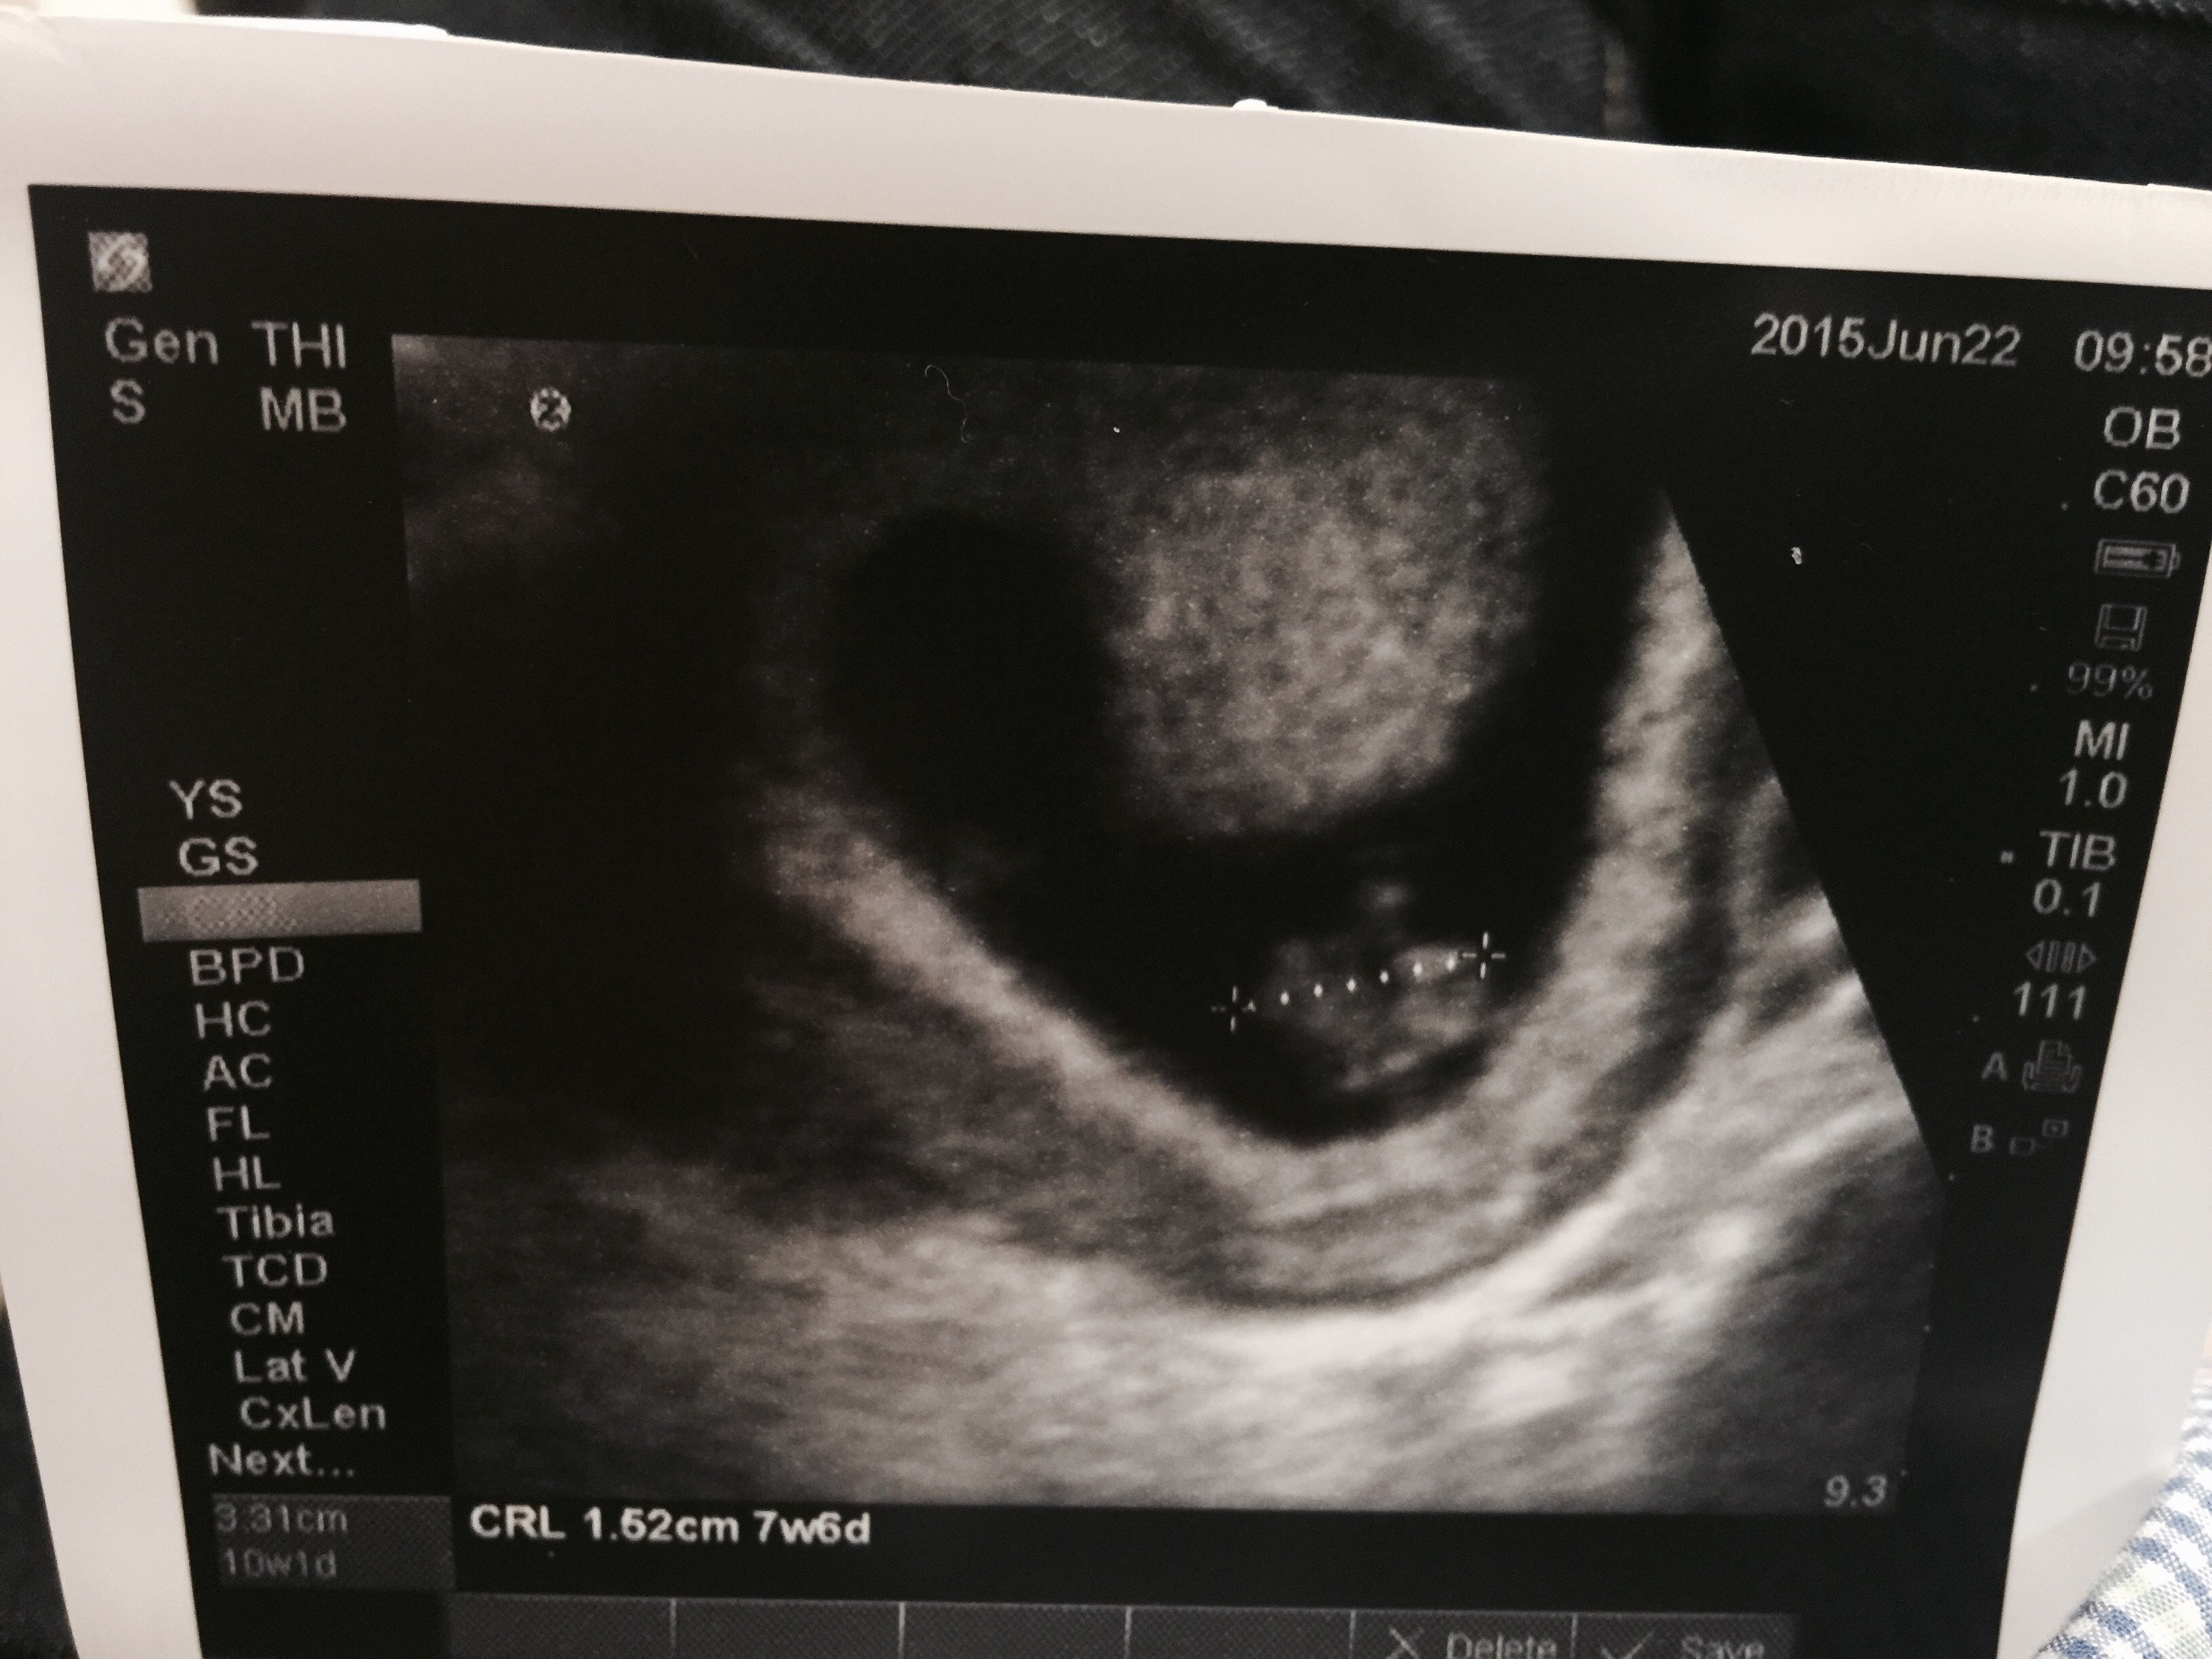

I know it is still early but some of you have already had your first ultrasound.

Feel free to share your picture(s) as you have them done!

Also be sure to include any information related to the U/S that you want to share with the group (how many weeks, heart rate, type of U/S, etc.).